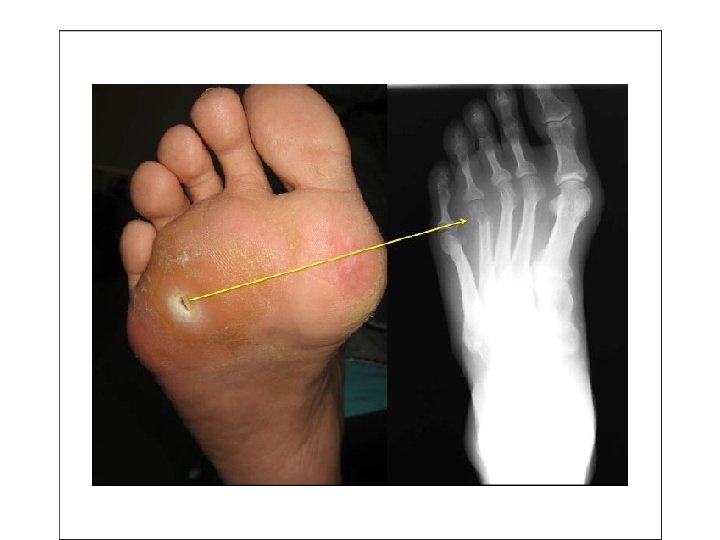

• In otherwise healthy children, most osteomyelitis is • hematogenous in origin and develops in the long bones. • - In adults, however, osteomyelitis more often occurs as a • complication of open fractures, surgical procedures, and • diabetic infections of the feet.

Affected bones • In children and infants (long bones of hands and legs) • In adult ( vertebrae , foot , maxilla and the body of mandible.